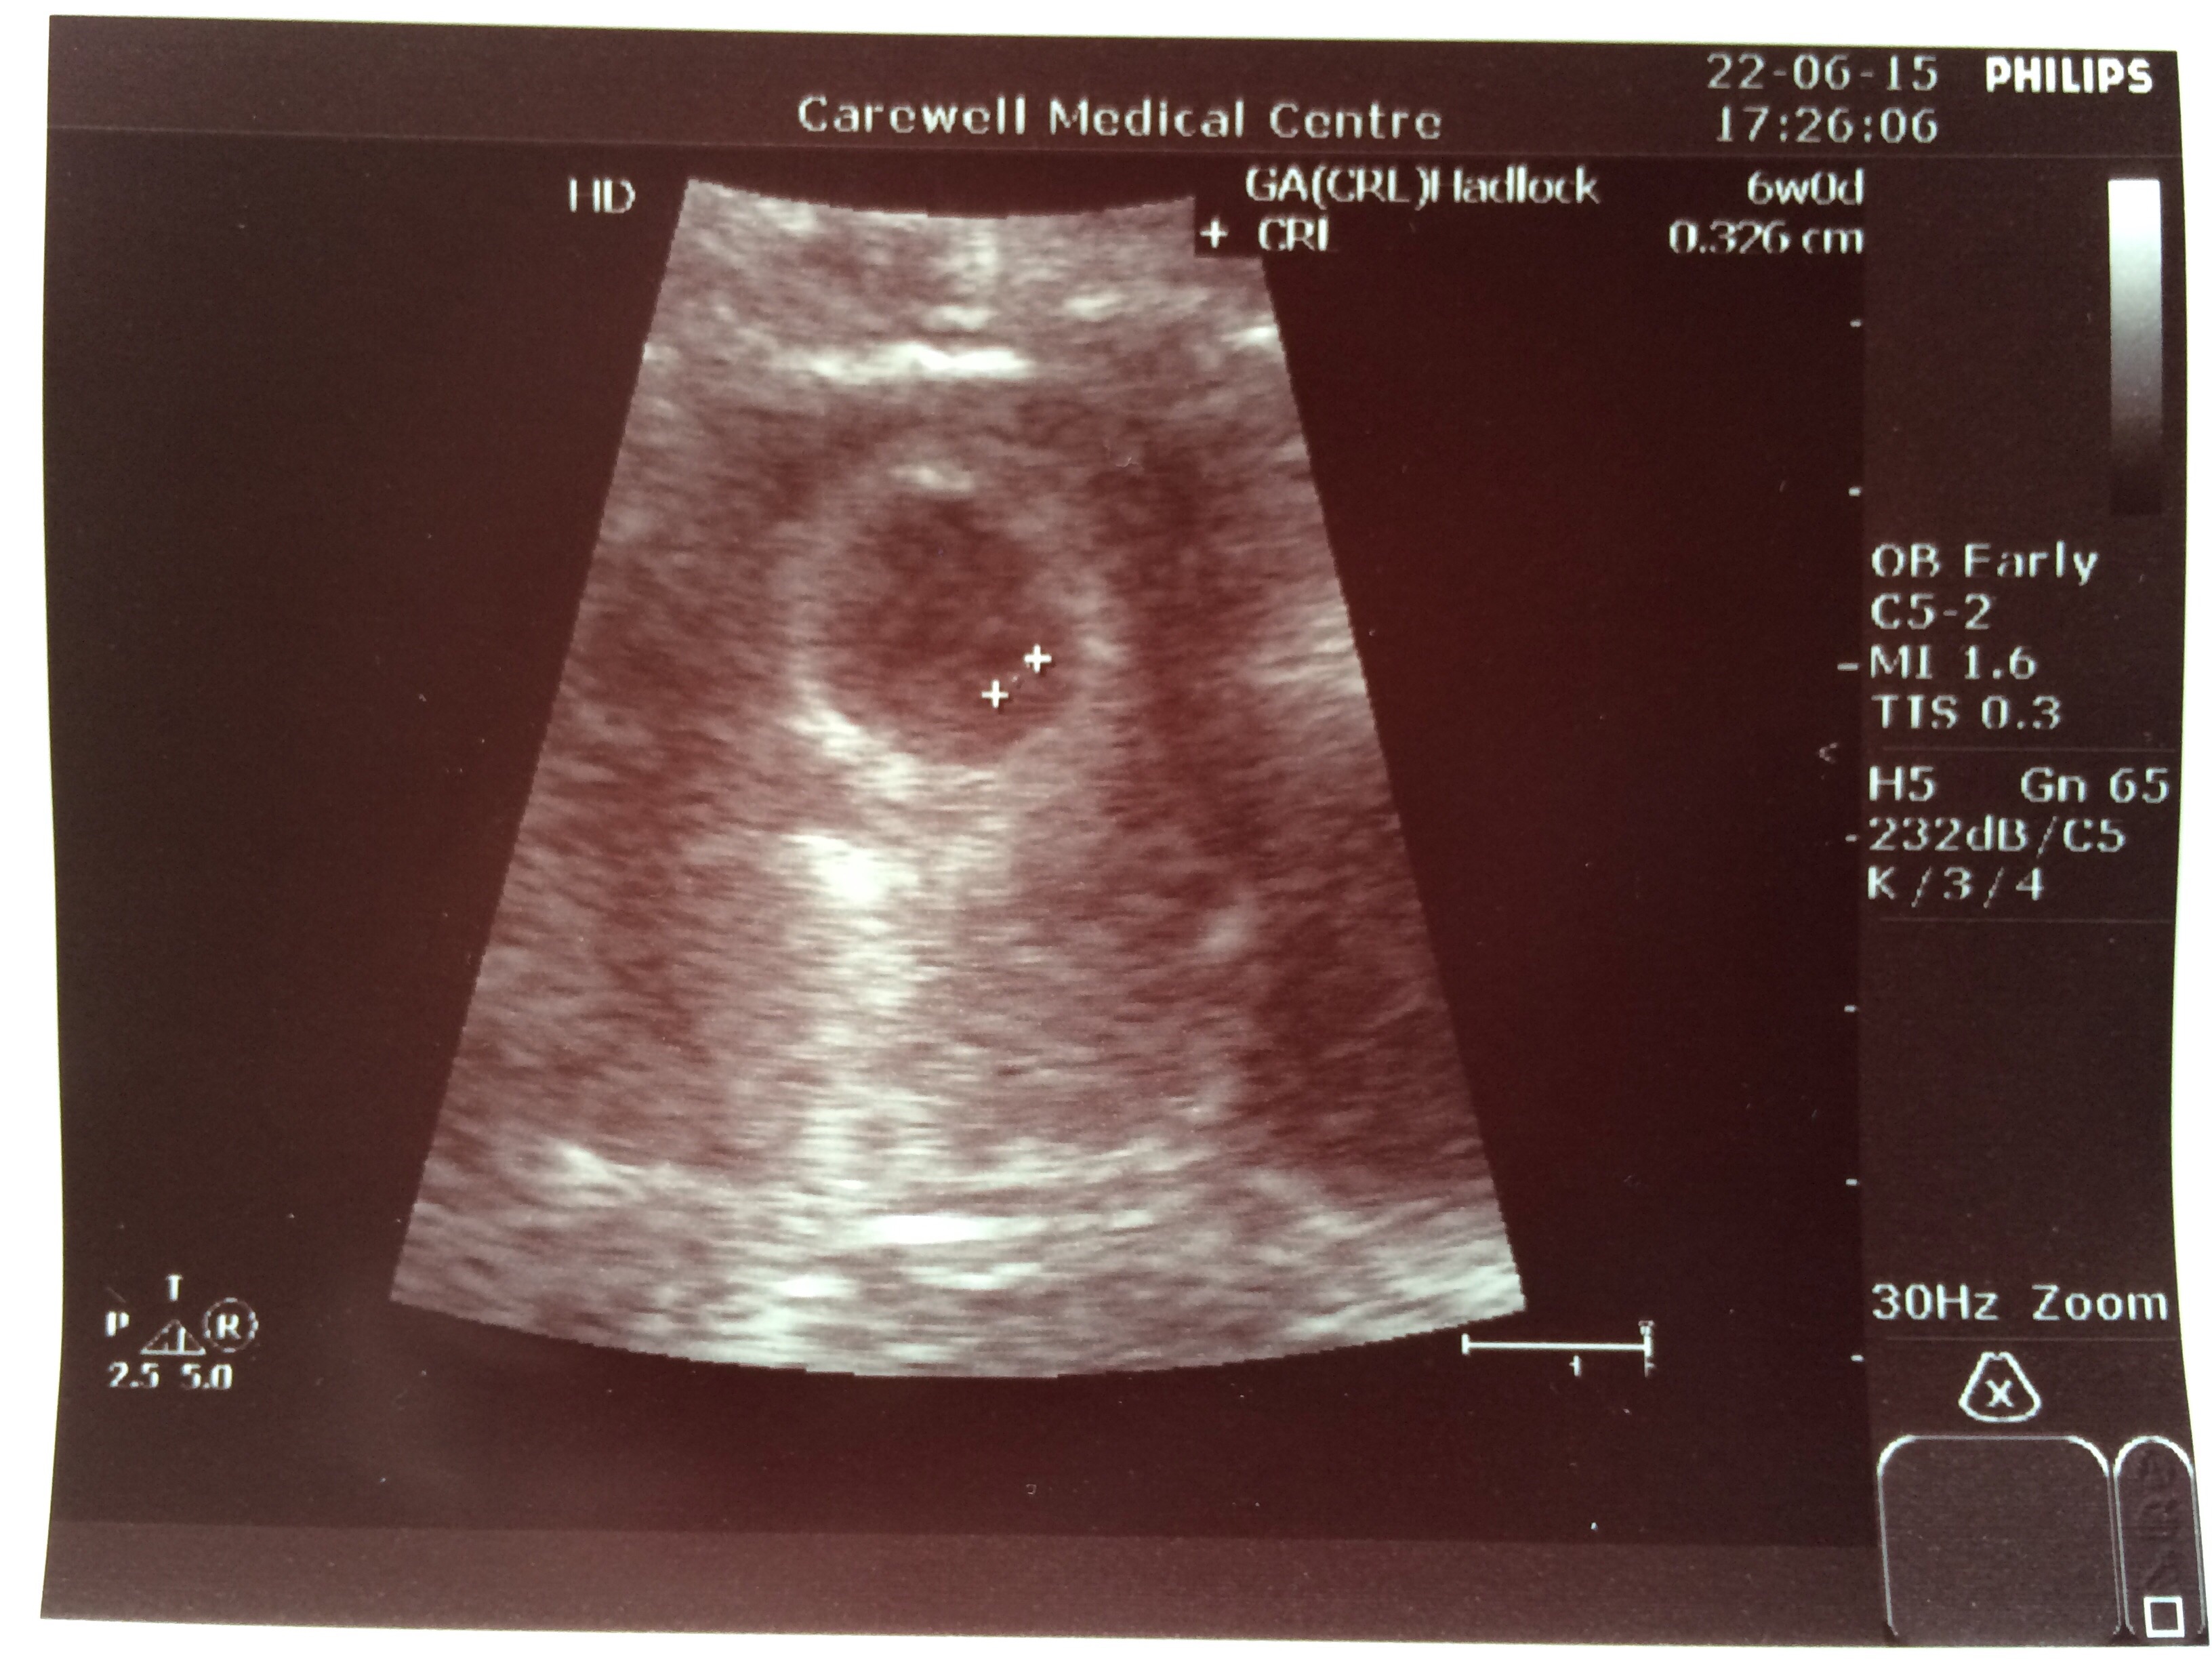

I know it is still early but some of you have already had your first ultrasound.

Feel free to share your picture(s) as you have them done!

Also be sure to include any information related to the U/S that you want to share with the group (how many weeks, heart rate, type of U/S, etc.).

EDD: 15th Feb 2016

125 bpm